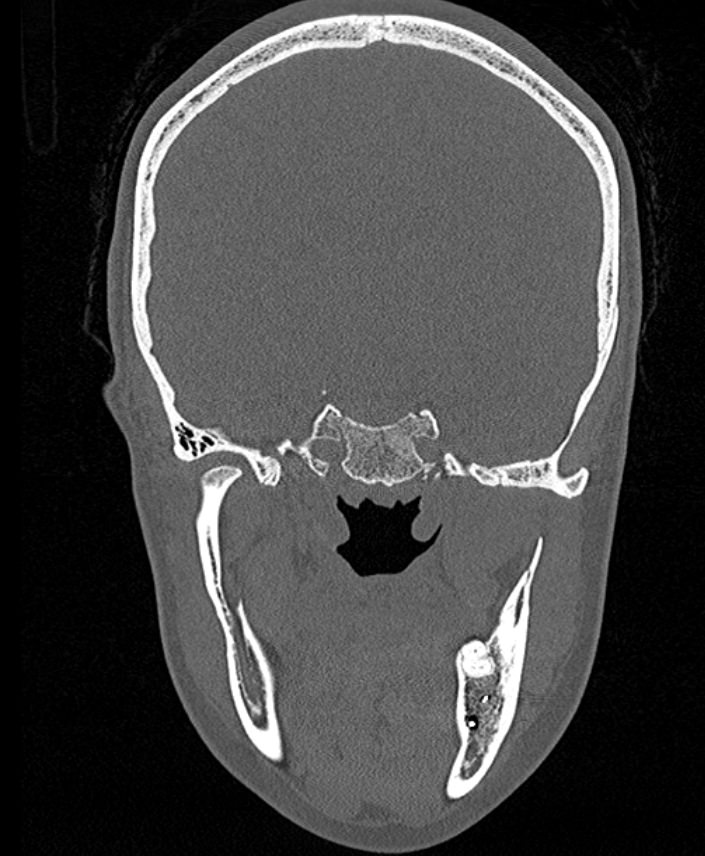

Мультиспиральная компьютерная томография относится к высокоинформативным лучевым методам исследования, то есть основана на применении рентгеновского излучения и различной способности тканей поглощать рентгеновские лучи. Костные структуры обладают наибольшей плотностью по сравнению с другими тканями, поэтому в большей степени поглощают рентгеновские лучи и лучше всего визуализируются при данном исследовании. Благодаря этому КТ позволяет детально изучить кости лицевого черепа, а также углубления, которые являются вместилищем для важных органов (глазницы, полость носа, ротовая полость).

КТ мягких тканей лица является наиболее информативным методом диагностики травматических повреждений лица, посттравматических деформаций, аномалий развития, инородных предметов в носовой полости и околоносовых пазухах. Кроме того, мультиспиральная КТ применяется для выявления скрытых воспалительных процессов, нарушений кровообращения в области лица, а также используется при планировании оперативного вмешательства (в том числе, пластических операций) и в дальнейшем применяется в послеоперационном периоде для оценки успешности проведенной операции.

Детальные изображения костей лицевого черепа и мягких тканей лица получаются за счет вращения трубки томографа с излучателями рентгеновских лучей вокруг объекта исследования. В аппаратах увеличено количество сверхчувствительных детекторов, позволяющих производить множество послойных снимков с толщиной среза от 0,5 мм, которые затем преобразуются в трехмерные пространственные модели лицевого черепа с окружающими тканями. Такие инновационные возможности аппаратов обеспечивают проведение точной и достоверной диагностики.